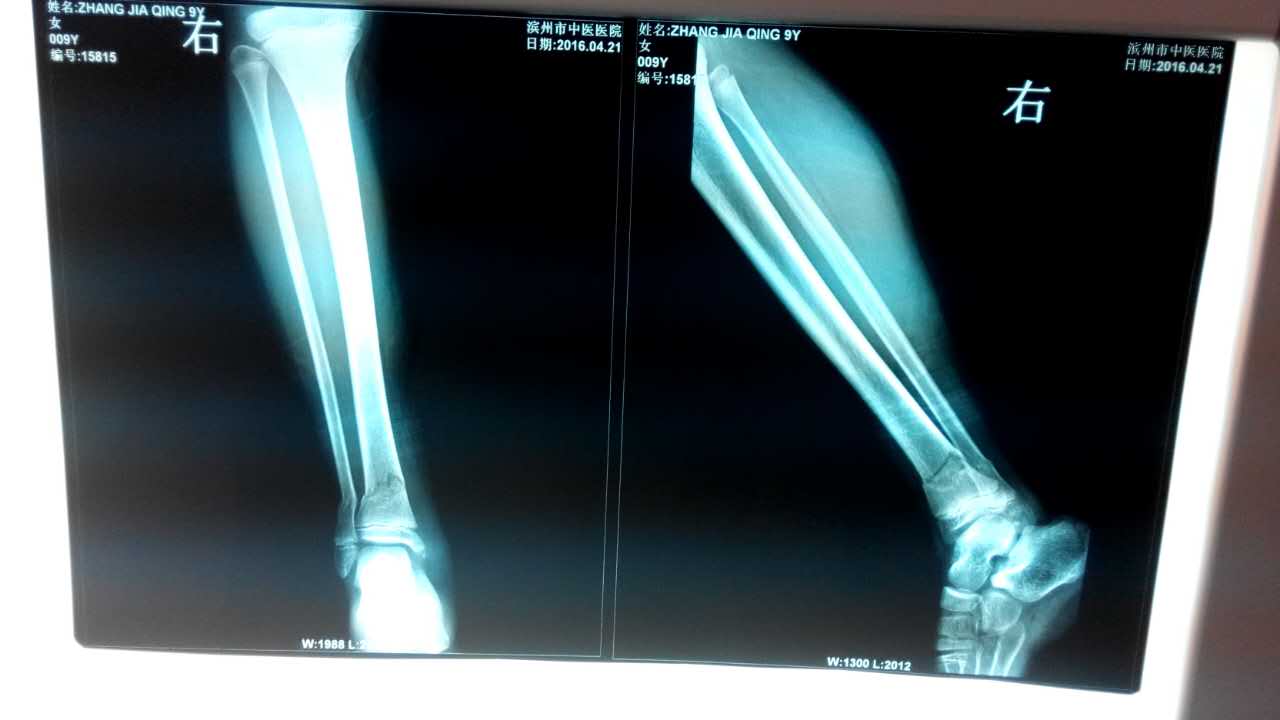

为了进一步贯彻执行省中医药管理局对骨伤科7种优势病种进行临床推广,进一步减轻病人负担,我院骨伤科自2014年12月份以来先后选派科内技术骨干分别到济南和文登正骨医院进修学习了经皮穿针内固定治疗锁骨骨折等7种优势病种的治疗方法并于近期在临床开展应用。2016年04月28日我院骨伤科在C型臂透视下成功完成了一例下肢胫腓骨双骨折病例,目前病人已康复出院。今后我们将继续开展此类手术。附病人手术前后X光片: